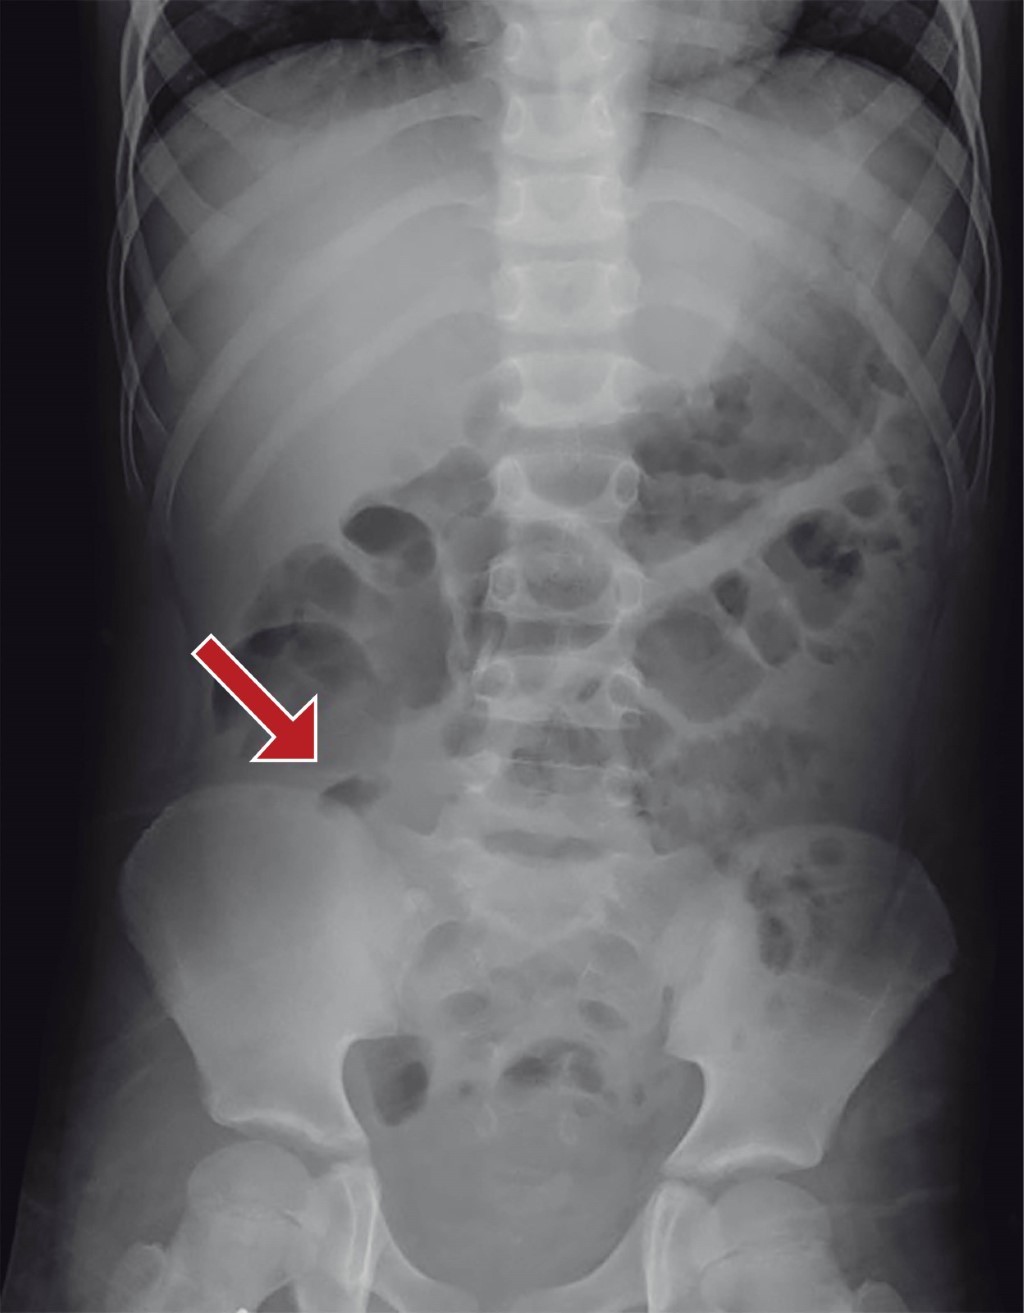

Masculino de nueve años con antecedente de haber sido intervenido quirúrgicamente por apendicitis aguda dos años y medio previos a su padecimiento actual, el cual inicia 10 días antes de su ingreso y se caracteriza por dolor abdominal generalizado y vómitos en dos ocasiones de características gastroalimentarias, manejado por facultativo con analgésicos no especificados y sin mejoría. Continúa con dolor abdominal de predominio en el cuadrante inferior derecho acompañado de náuseas y vómitos. Motivo por el cual acude al Servicio de Urgencias del hospital, en donde se encuentra al paciente con dolor en cuadrante inferior derecho, posición en gatillo y con datos de irritación peritoneal. Se solicitan laboratoriales, reportándose hemoglobina de 13.0 mg/dl, hematocrito de 38.2%, 15.15 × 109, 76.4% neutrófilos. La placa simple de abdomen muestra una imagen de asa fija en fosa iliaca derecha (Figura 1). Se solicita ultrasonido abdominal, el cual reporta una colección de 5 × 4 cm (Figura 2), por lo que se interconsulta al Servicio de Cirugía General ya que no se contaba con cirujano pediatra en el turno; 24 horas después de su ingreso es valorado por cirugía, encontrando al paciente con discreta resistencia voluntaria en cuadrante inferior derecho e irritación peritoneal. Se solicita una resonancia magnética abdominal, para determinar la probable etiología de la colección, la cual reporta una colección amorfa en fosa iliaca derecha, de bordes irregulares y bien definidos, con medidas de 5.1 × 4.3 × 4.9 cm en sus diámetros longitudinal y anteroposterior transverso, respectivamente, compatibles con absceso en fosa iliaca derecha.

Figura 1